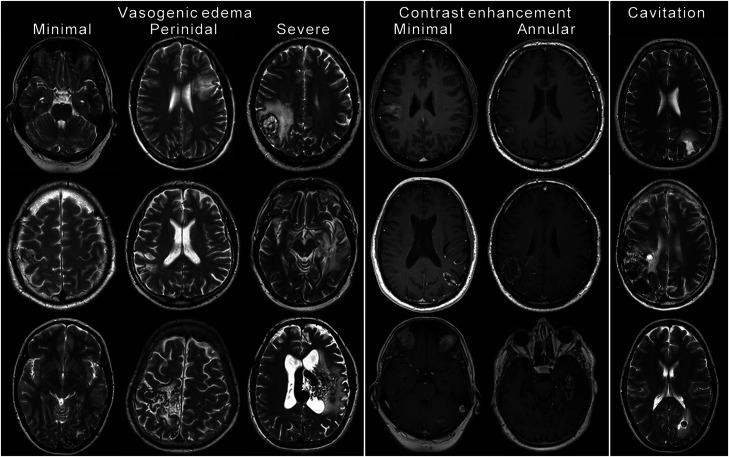

Retrospective review of pre- and post-treatment digital subtraction angiography and MRI and medical records in 30 patients with AVMs treated with proton radiation. Patients were treated with two or five fractions; total radiation dose was 20-35 physical Gy. Vasogenic edema (minimal, perinidal, or severe), contrast enhancement (minimal or annular), cavitation and nidus obliteration (total, partial, or none) were assessed.

26 of 30 patients (87%) developed MRI changes. Vasogenic edema was seen in 25 of 30 (83%), abnormal contrast enhancement in 18 of 26 (69%) and cavitation in 5 of 30 (17%). Time from treatment to appearance of MRI changes varied between 5 and 25 months (median 7, mean 10). Seven patients developed new or deteriorating symptoms that required treatment with corticosteroids; all these patients had extensive MRI changes (severe vasogenic edema and annular contrast enhancement). Not all patients with extensive MRI changes developed symptoms. We found no relation between MRI changes and nidus obliteration.